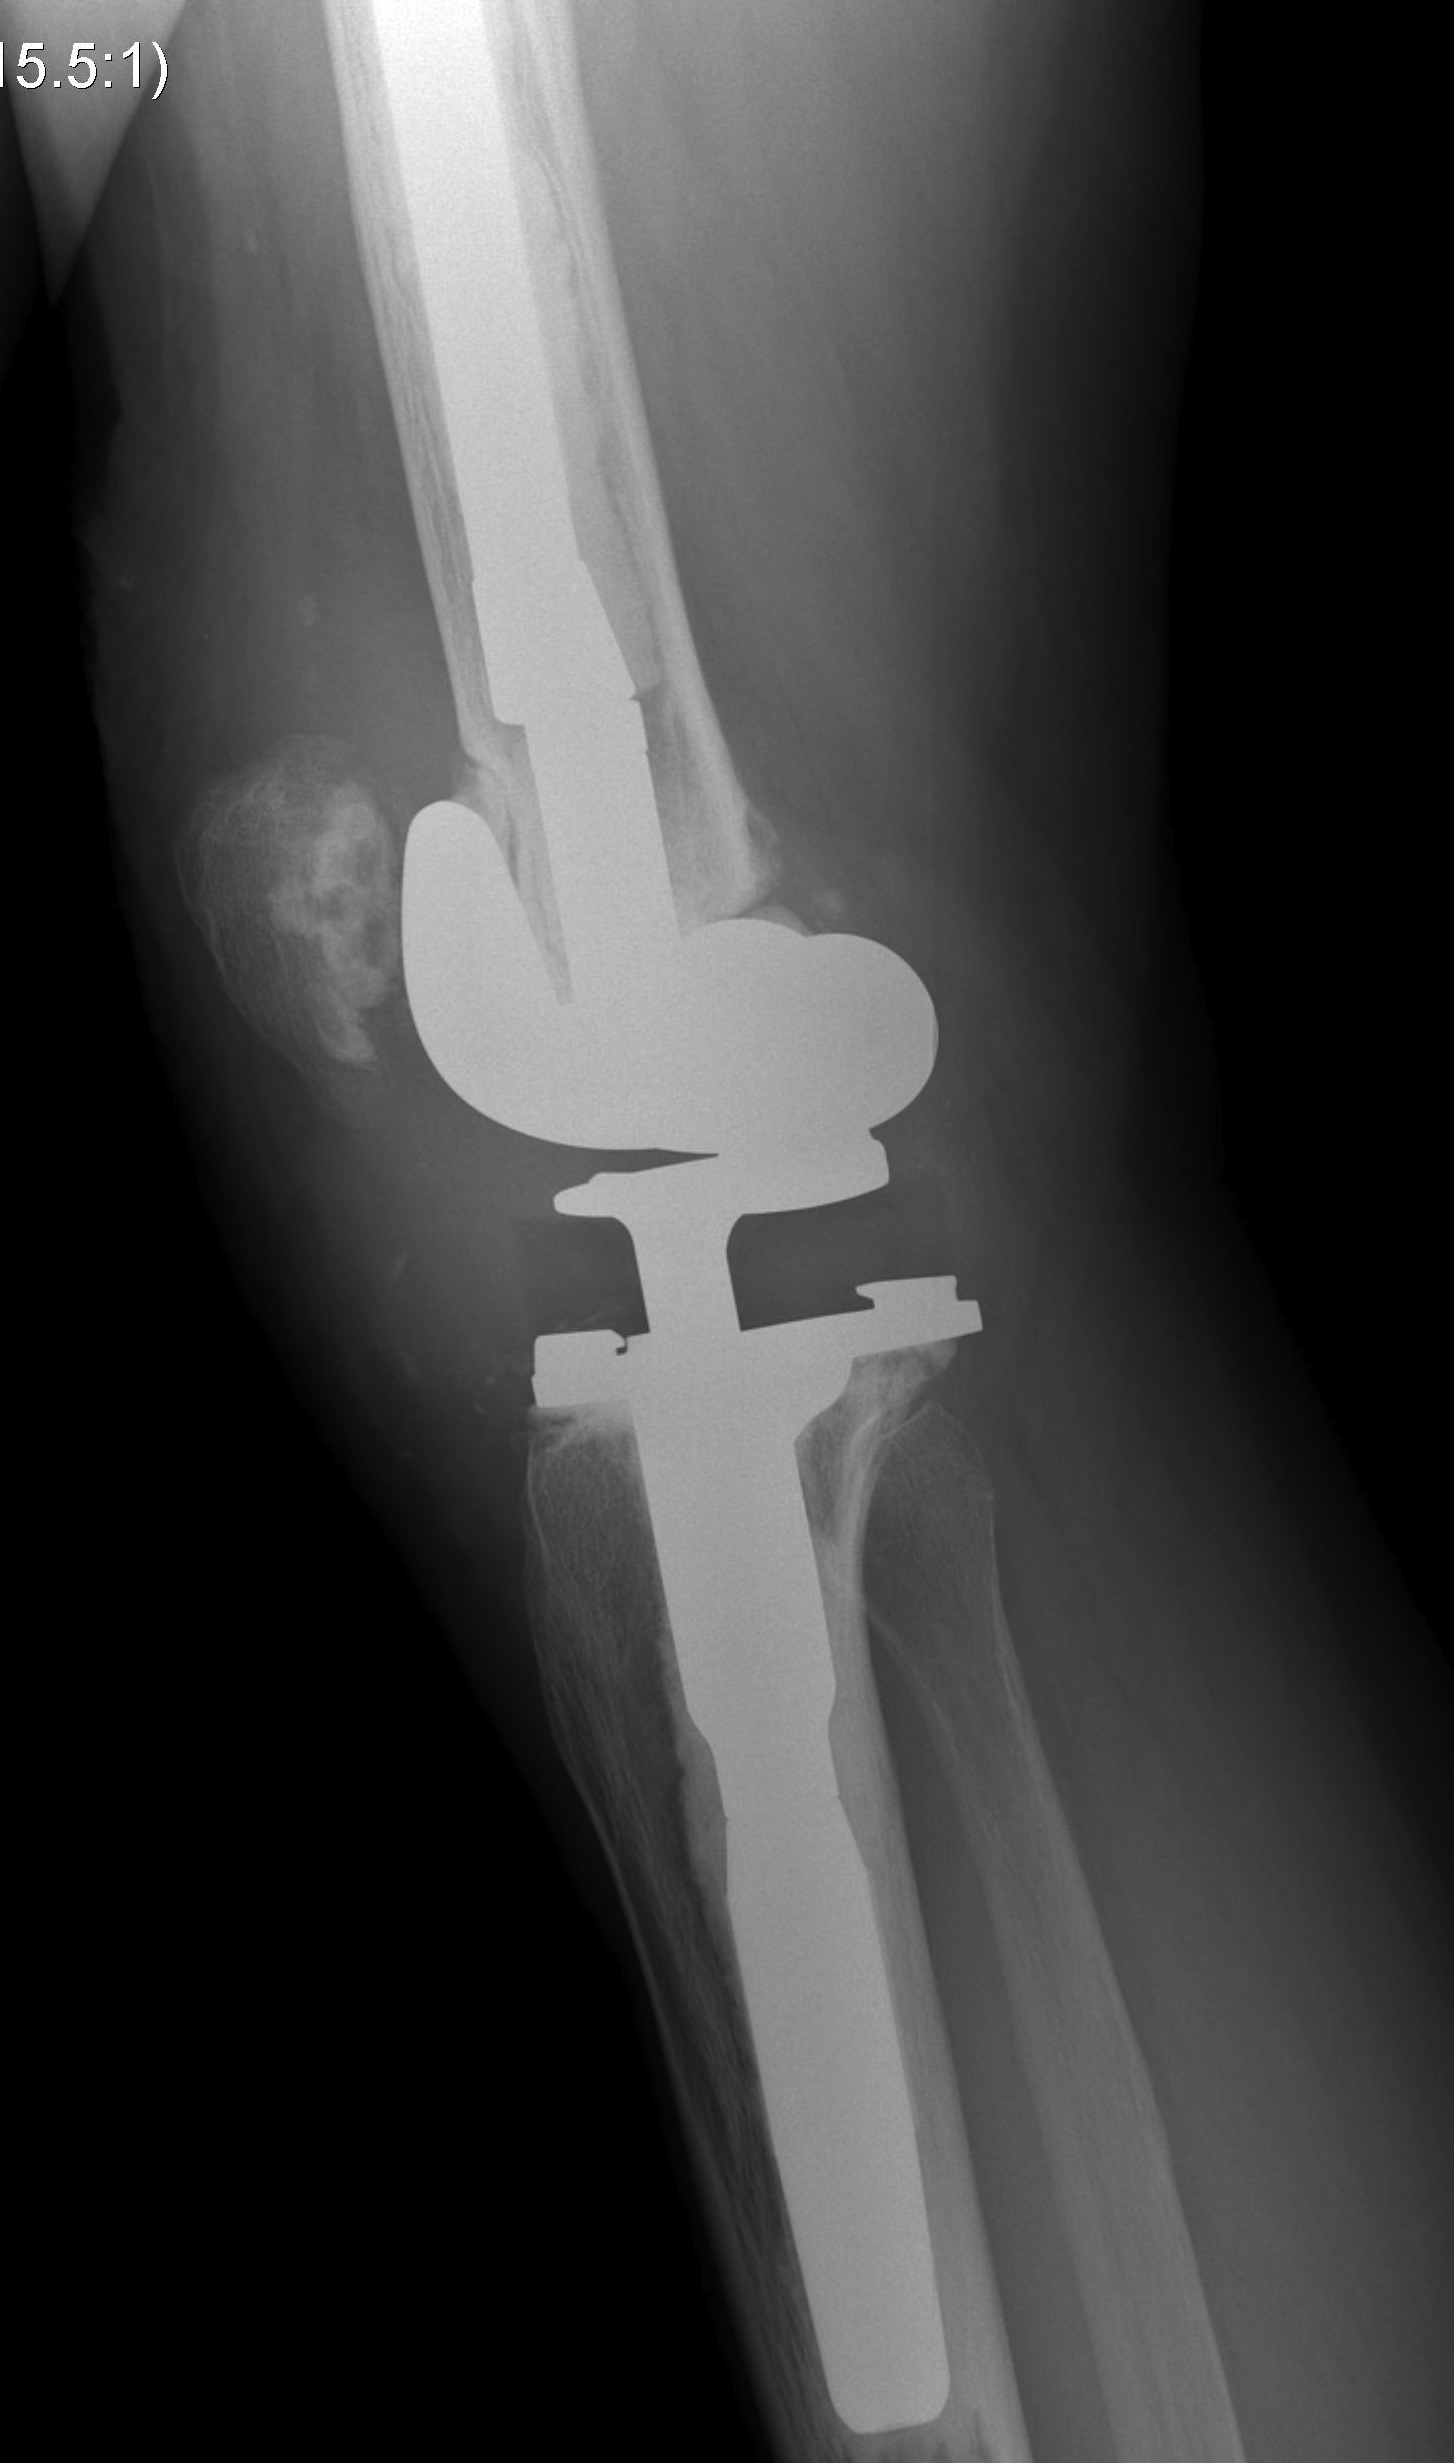

3. Tibial tuberosity osteotomy

- 6-10 cm long, 2 cm wide, 1 cm thick

- lateral periosteum intact / lever open laterally

- bypass osteotomy with stem

- need to wire back around the tibial stem

- place wires before definitive stem

- drill holes medially and laterally

- can use diverging screws as well